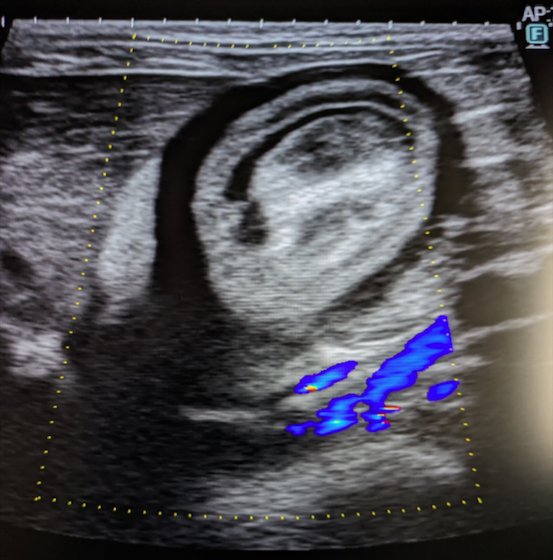

犬猫共に、膀胱内に腫瘤が発生することがあり、その場合には排尿しづらそうな様子や、血尿、頻尿といった、膀胱炎などと同様の症状がよく認められます。超音波検査を行うことで、膀胱内に腫瘤が形成されているかどうかを確認することが出来ます。また、カテーテルを用いて採材を行い、細胞診検査や遺伝子検査を行うことで診断を行います。診断後、腫瘤の発生状況などにより、外科的/内科的治療を検討していきます。膀胱内腫瘤を認めた場合には悪性腫瘍であることが比較的多いこともあり、普段と異なる排尿の様子が認められた場合などは、お早めにご相談下さい。

獣医師 池田